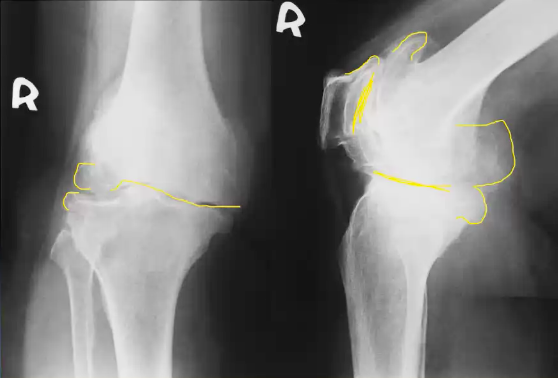

This 75 year old woman presented with difficulty walking and knee pain. How would you describe these X-rays?

A 30 year old man presented to the ED with left knee pain after a cycling accident.

On examination there was no deformity, but it was painful for him to weight-bear. Movements of his knee were painful, and this limited his movements.